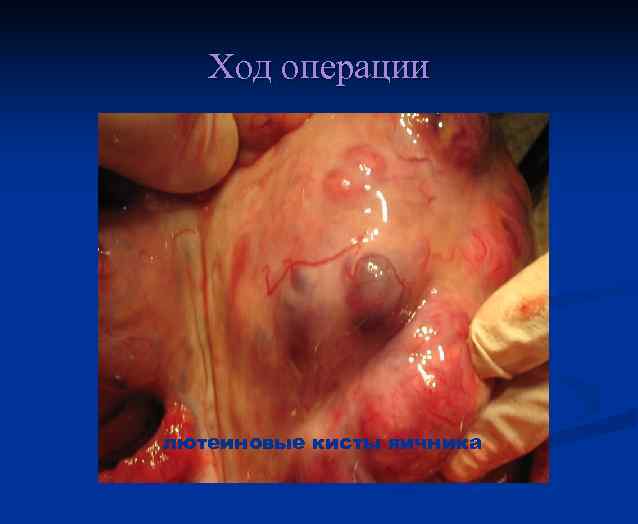

Клиника n n Нарушение менструальной функции(у 53, 7 % позднее менархе). Несоответствие размеров матки предполагаемому сроку беременности (у 50— 86 % больных). Образование лютеиновых кист яичников (в 50 % случаев). Появляются в течение первых 2 нед. Наличие их служит неблагоприятным прогностическим признаком. Обратное развитие лютеиновых кист отмечается в течение 3 мес. после удаления пузырного заноса. Малигнизации пузырного заноса. Злокачественное течение трофобластической болезни отмечено у 44, 2 % больных с размерами матки больше предполагаемого срока беременности.

Хориокарцинома матки с лютеиновыми кистами яичников

Факторы риска малигнизации хорионэпителиомы возраст больных старше 40 лет n позднее начало менструаций n несоответствие размеров матки сроку беременности n наличие лютеиновых кист яичников n

Ход операции лютеиновые кисты яичника

Ход операции Левый яичник с лютеиновыми кистами